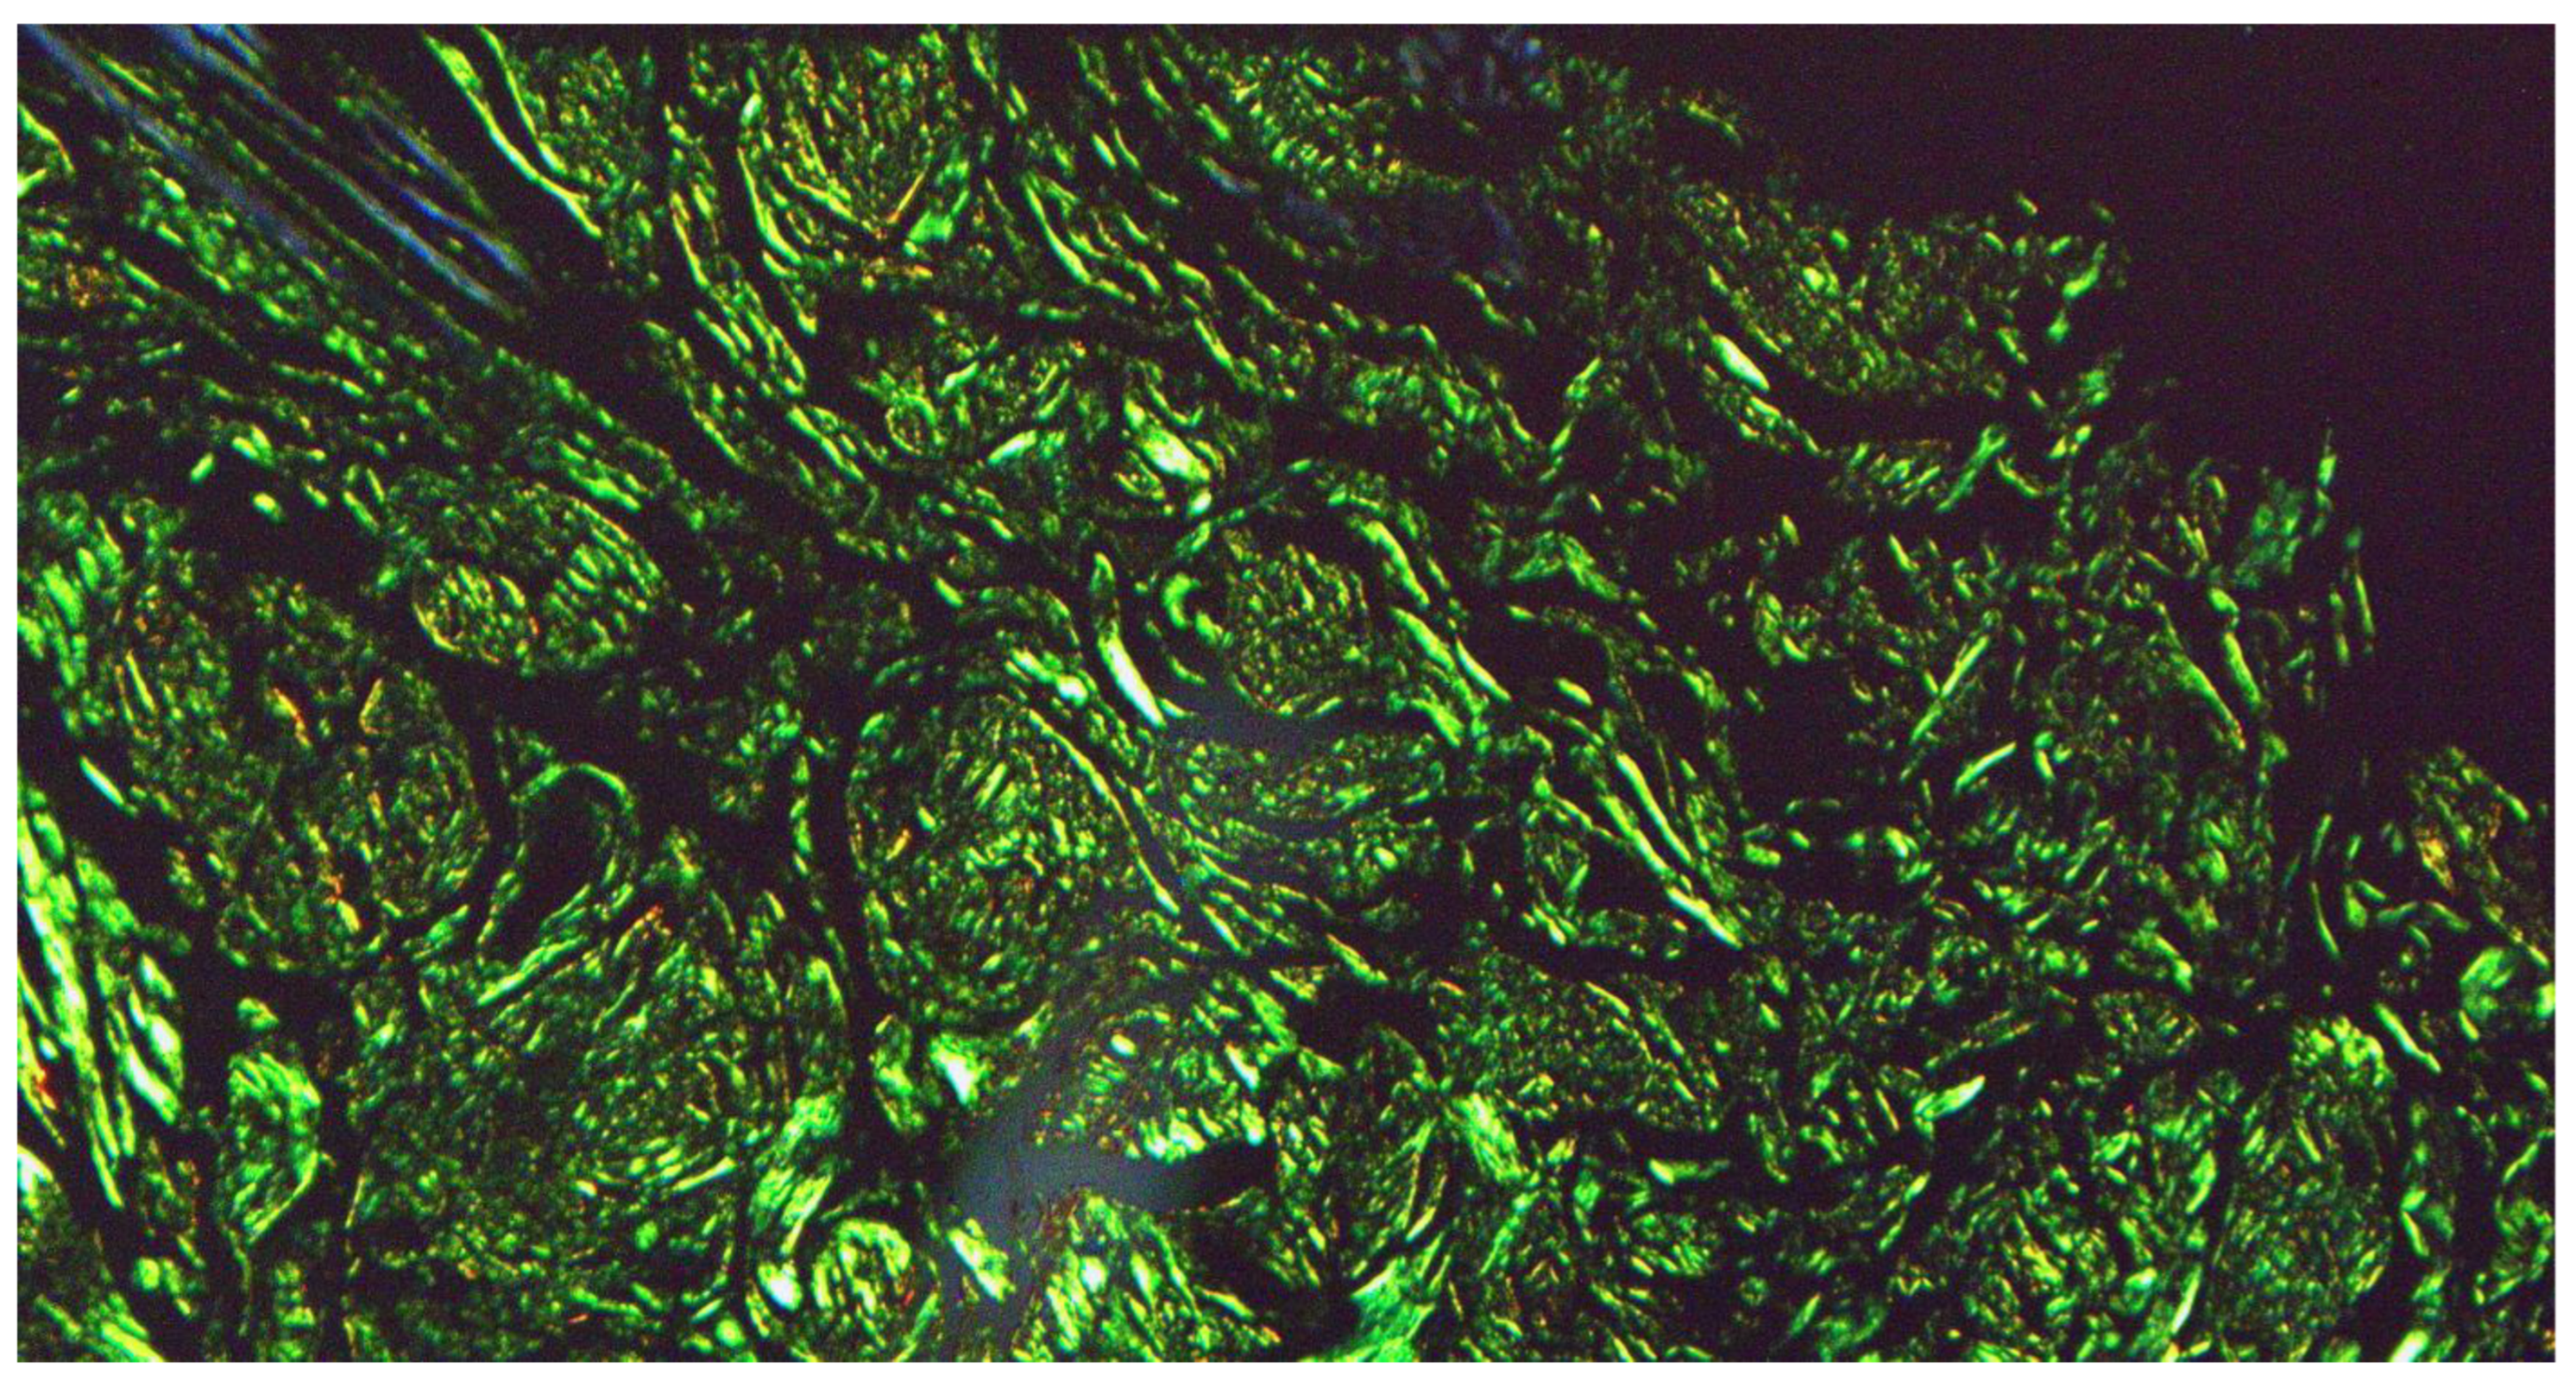

At our clinic, for a diagnosis of certainty regarding LA, an incisional biopsy was performed regarding the typical infiltrated plaques on the lower limbs. The histopathological investigations reported typical LA findings, such as the deposition of amyloid material at the papillary dermis, beneath the dermo-epidermal junction; there were also some areas with inconsistency regarding the melanic pigment and diffuse inflammatory infiltrate at the middle and superficial dermis. The epidermis was not interested in this infiltration and acts as an innocent bystander with acanthosis, hyperkeratosis, and elongation of the epidermal ridges (Figure 3, Figure 4 and Figure 5). With polarized microscopy, it was possible to appreciate the amyloid deposits beneath the dermo-epidermal junction (Figure 6).

Different types of PLCA are frequently recognized by common histological features such as PAS positivity, affinity for thioflavin T and Congo Red, and metachromasia following staining with crystal violet or methyl violet. When examined under polarized light, amyloid exhibits distinctive apple green birefringence, also known as dichroism, due to the use of Congo Red. Frequently, amyloid is located in the lichenoid (papular) and macular patterns in the papillary dermis, beneath the dermo-epidermal junction; the acanthosis and hyperkeratosis of the underlying epidermis are frequently observed, and neither macular nor lichenoid amyloidoses involve blood vessels [10,11]. A loose network of unbranched filaments with a diameter of 7.5–10 nm is visible under electron microscopy. The fibrillary anti-parallel beta-sheet structure of the various amyloid precipitates is what unites them ultrastructurally. Protofilaments make up the filaments, and the filaments group together to form fibrils. The fibrils are present in the extracellular space, fibroblasts phagocytose minute amounts of them, and a degeneration of keratinocytes known as filamentous and pyknotic degeneration has been documented in the literature. It is possible that fibroblasts play a direct role in the production of amyloid; however, particular studies on this matter are currently lacking. Unlike the corresponding amyloid protein, the amyloid P component exhibits a pentagonal ultrastructure and is non-fibrillary [12].

Figure 6. Histological photomicrograph showing characteristic apple green birefringence at polarized microscopy (preparation for Congo Red; original magnification 20×).